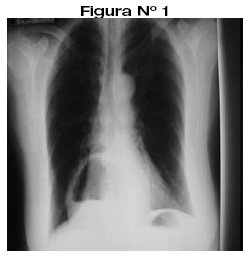

<body><![CDATA[<p align="justify"><font face="Verdana" size="2">Se trata de un paciente de 50 años de edad, de sexo femenino, que acude al servicio de diagnóstico por imágenes para exámenes radiológicos de rodillas, columna dorsolumbar y test de Farrel; observándose incidentalmente en la radiografía de columna imágenes de anormalidad y luego se indica radiografía de tórax PA y Lat. donde se observa imagen radioopaca con nivel hidroareo (<a href="#f12">Figura N&deg; 1,2</a>). </font></p>     <p align="justify"><a name="f12"></a></p>     <p align="center"><img src="/img/revistas/rmcmlp/v18n2/a06_figura_01.jpg" width="252" height="257"></p>     <p align="center">&nbsp;</p>     <p align="center"><img src="/img/revistas/rmcmlp/v18n2/a06_figura_02.jpg" width="293" height="239"></p>     <p align="justify"><font face="Verdana" size="2">Se complementa el mismo con un examen contrastado de esófago y estómago, observándose que el cardias, el estómago y parte del duodeno se hallan por encima del hiato o sea en la cavidad torácica. (<a href="#f3">Figura N&deg; 3</a>).</font></p>     <p align="justify"><a name="f3"></a></p>     <p align="center"><img src="/img/revistas/rmcmlp/v18n2/a06_figura_03.jpg" width="301" height="266"></p>     <p align="center">&nbsp;</p>     <p align="justify"><font face="Verdana" size="3"><b>DISCUSIÓN</b></font></p>     ]]></body>

<body><![CDATA[<p align="justify"><font face="Verdana" size="2">Se revisa el presente caso por constituir un hallazgo radiológico incidental y se demuestra esta patología tanto por el examen radiológico simple de tórax como por el examen radiológico contrastado (SEGD).</font></p>     <p align="justify"><font face="Verdana" size="2">El diagnóstico se realiza con una radiografía de tórax PA y Lateral y se confirma con el examen contrastado de esófago y estómago.(SEGD).</font></p>     <p align="justify"><font face="Verdana" size="2">Para demostrar pequeñas hernias, es necesario que el examen contrastado se realice en decúbito dorsal, ya que se reducen en posición de pie.</font></p>     <p align="justify">&nbsp;</p>     <p align="justify"><font face="Verdana" size="2"><b>CONFLICTO DE INTERESES:</b></font></p>     <p align="justify"><font face="Verdana" size="2">Los autores del presente caso clínico declaran no tener ningún conflicto de intereses</font></p>     <p align="justify">&nbsp;</p>     <p><font size="3"><b><font face="Verdana, Arial, Helvetica, sans-serif">Notas</font></b></font></p>     <p align="justify"><font face="Verdana" size="2">*      Jefe del Servicio de Diagn&oacute;stico por Im&aacute;genes. Hospital Materno Infantil. C.N.S.</font></p>     <p align="justify">&nbsp;</p>     ]]></body>